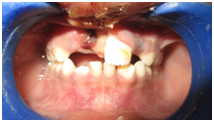

A 10year old boy reported to the department of Pedodontics with a chief complaint of missing upper front tooth and gave a history of fall from bike while 5 days back. They had been to pediatrician for the lacerated lip and got it sutured. Parents had kept the avulsed tooth in paper without knowledge of reimplantation of the same tooth. Patient had no relevant medical and family history. On examination swelling and suture was present on upper lip, lacerated gingiva with healing socket in 11 regions. 21 was intact, vital and non mobile. (Figure 1) (Figure 2) On examination of avulsed tooth 11, it was found to have open apex (Figure 3). On intraoral radiographic examination, no fracture was seen with alveolar bone (Figure 4). Thus avulsed tooth was cleaned and debrided with soft pumice prophylaxis, gentle scaling was done to remove ligament remnants. It was then placed in 1.23% sodium fluoride for 15minutes. Extraoral endodontic therapy was also done using retrograde filling of MTA (Figure 5). Local anesthesia was administered and socket was cleaned, curetted and irrigated to remove clot and debris and 11 was slowly reimplanted in socket. Orthodontic wire – composite splinting was done for 4weeks as the dry storage was more than 60minutes (Figure 6). Systemic antibiotics amoxicillin and doxycycline were prescribed for 5days. The patient was recalled after 1 month and splint was removed. No mobility was present. Again patient was recalled after 2months to check the condition (Figure 7). Again patient was recalled after 6months; tooth had slightly discolored but was not mobile and maintained the space (Figure 8). Patient was happy and contended with the reimplantation of his own tooth without disturbing his original look.

Figure 3 Avulsed 11.